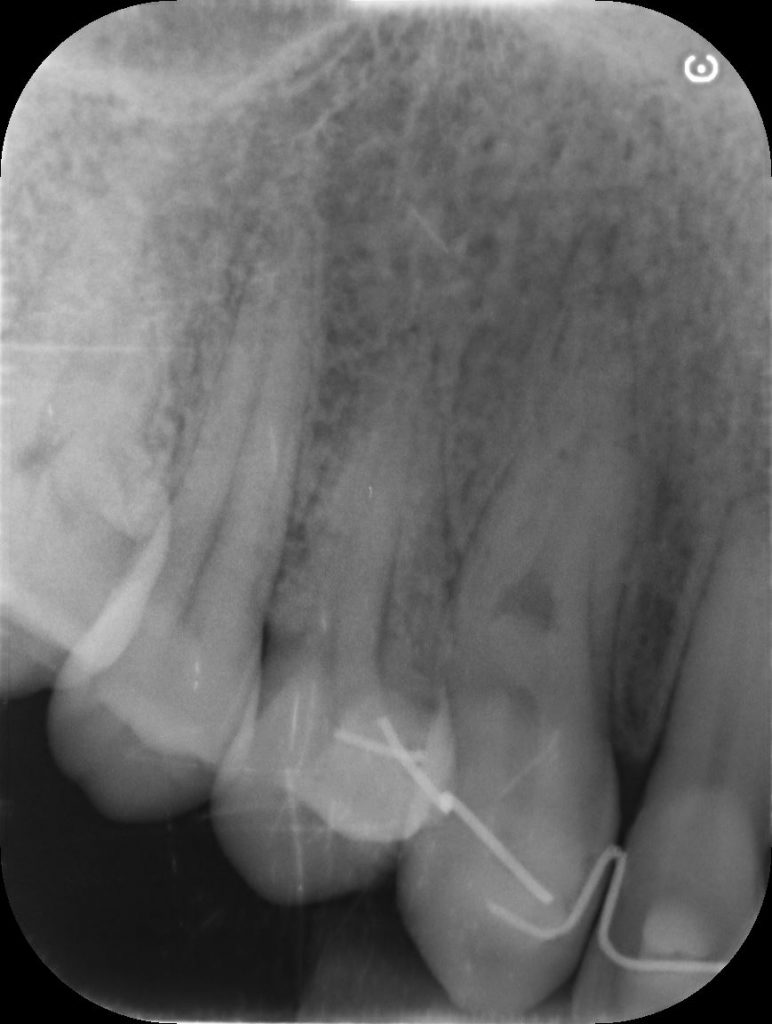

The 37-year-old patient had a class III external resorption of the root of 13#.

The cbct showed a lesion of about 4mm in diameter, which vestibularly affected the root #13, just below the junction.

RX